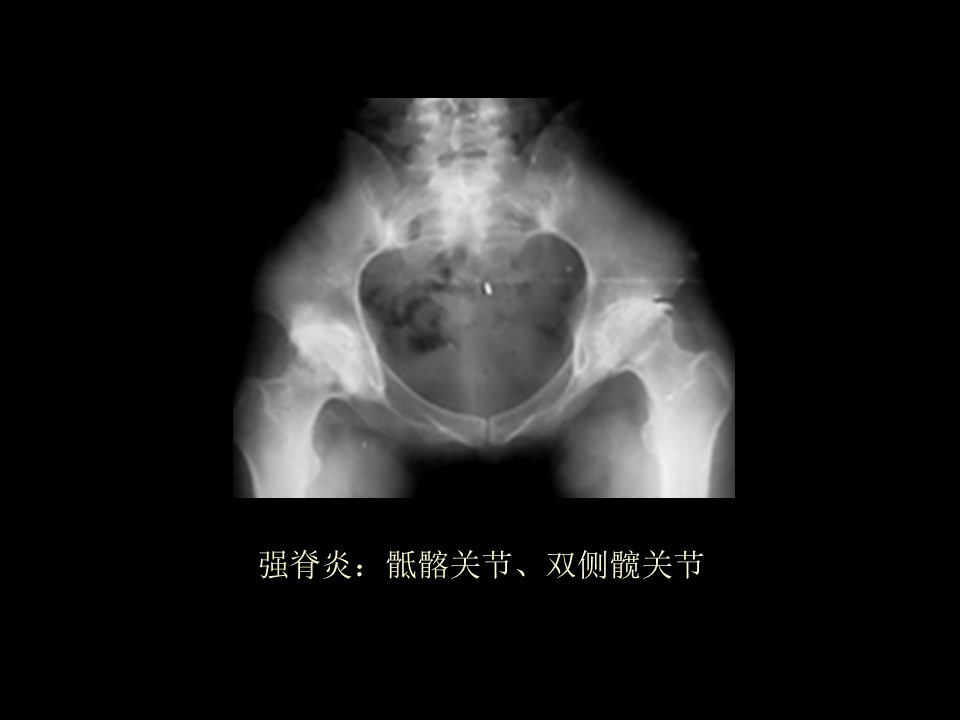

强直性脊柱炎的护理PPT 强直性脊柱炎是以中轴关节慢性炎症为主,原因不明的全身性疾病。其特点为累及骶髂关节常发生椎间盘纤维环及其附近韧带钙化和骨性强直。...